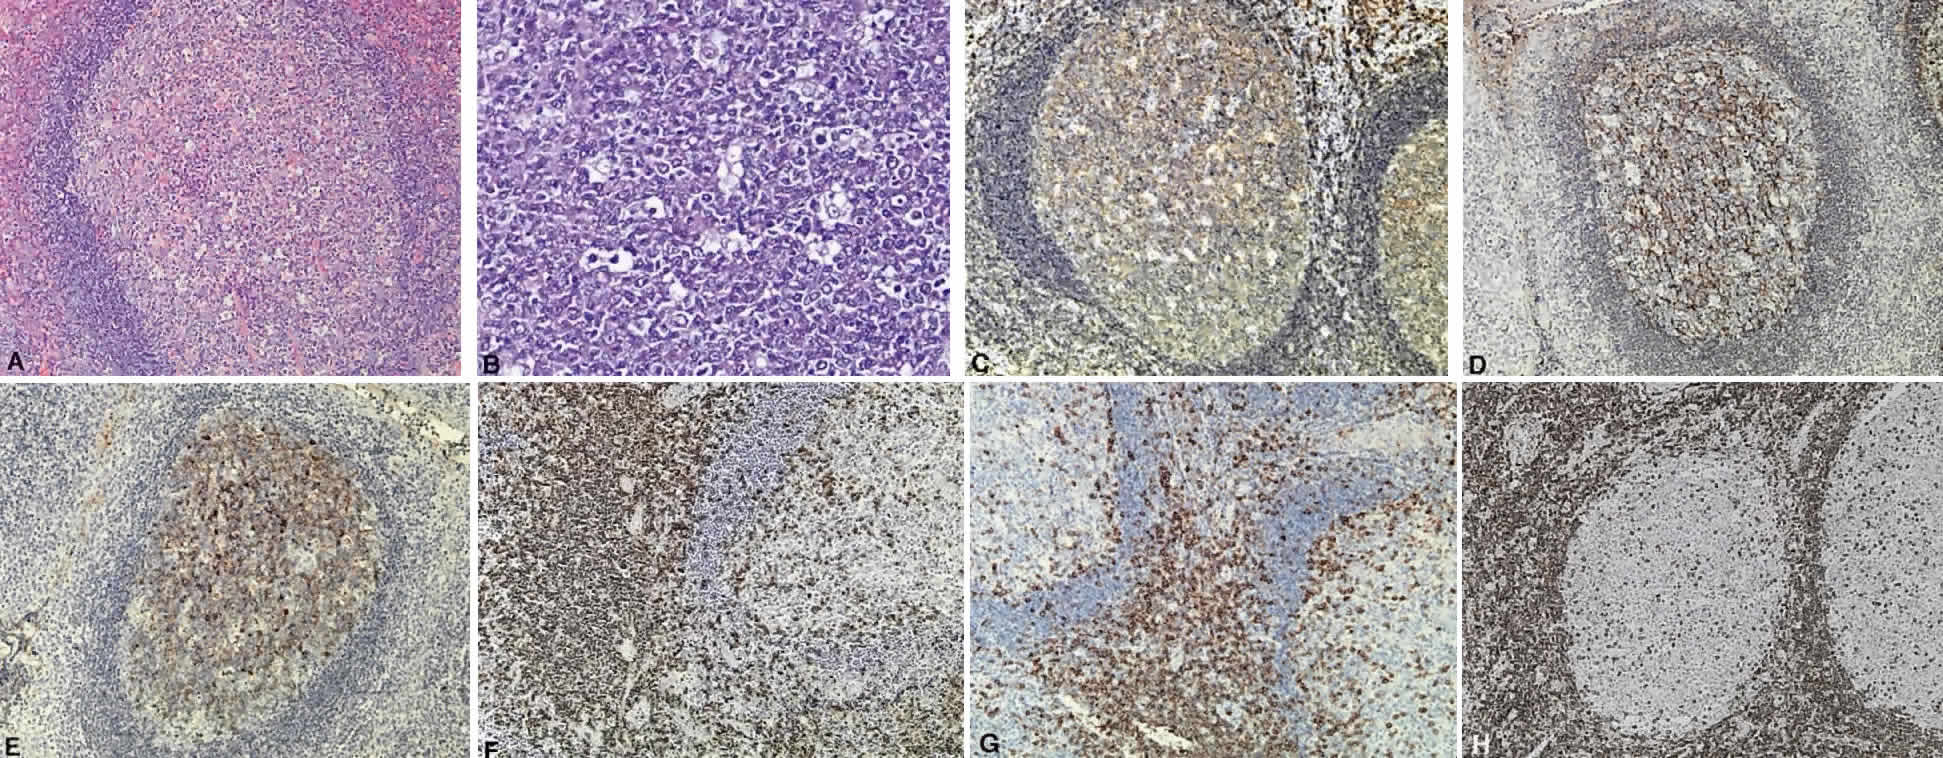

B cells arise from the bone marrow and produce immunoglobulin in a humoral response. T cells are thymus-derived and respond in a cell-mediated reaction via cells that are antigenically marked or produce lymphokines. Circulating blood and lymph nodes normally have a ratio of 70% T cells and 30% B cells, natural killer cells, or null cells. The normal lymph node is composed of follicles, each with germinal centers, mantle zones, and surrounding cortex (Fig. 2). The germinal center is composed of a framework of dendritic histiocytes, follicular dendritic cells, centroblasts, centrocytes, immunoblasts, small lymphocytes, and tingible body macrophages, whereas the surrounding cortex and paracortex consist mainly of B and T cells, respectively. Lymphomatous B cells were initially identified histologically using heterosera against immunoglobulin, which could then be stained with immunoperoxidase stain or rendered fluorescent with immunofluorescent markers.1b Plasma cells could be similarly identified by their cytoplasmic immunoglobulin. T cells were first identified cytologically by their rosette formation when combined with sheep erythrocytes.2 In addition, they were noted to uniquely contain cytoplasmic alphanaphthyl esterase, for which they could be stained histologically.3 Information regarding B-cell clonality could be obtained by staining for immunoglobulin, in particular, kappa and lambda light chains. In benign lesions, the kappa-lambda ratio of B-cell production is 2:1, whereas in malignant lesions, the ratio increases to 10:1.3 Benign and atypical reactive lesions have 50% or greater T cells, whereas malignant B-cell lesions usually consist of only 10% to 20% T cells.3 Malignant T-cell lymphomas, on the other hand, consist of 90% T cells.3 In reactive lesions, the T-cell helper-to-suppressor ratio is increased from the normal 2:1 to 5:1, whereas the normal ratio is maintained in malignant B-cell lymphoma.3 Thus, information about cell lines and immunoglobulin can be used to determine the predominant cell type, the cell type ratio, and the monoclonality or polyclonality of the B-cell population from the immunoglobulin expressed. Reactive processes have been thought to result from polyclonal or oligoclonal populations wherein every distinct clonal population expresses a distinct gene rearrangement, whereas a malignant lymphoma is thought to arise from a monoclonal clone population, which would express only a single gene rearrangement. Polymerase chain reaction has been used to specifically amplify clonal immunoglobulin gene rearrangements. In addition, cell surface markers of the various cell lines have been identified, beginning with the immunoglobulins and interleukins, and, later, cell surface antigen receptors, termed clusters of differentiation (CD), which are used to characterize the degree of differentiation of the cell type in question.4,5 The list of identified cell surface markers subsequently has expanded to over 100 and has aided in the characterization of Hodgkin's lymphoma and different subsets of nonHodgkin's B- and T-cell lymphomas6 (Table 1).

While the Lukes-Collins and Working Formulation classifications were in wide use in the United States, the European literature made references to the Kiel and updated Kiel classifications, which led to disparities in classifying lymphoma. Another classification proposed by Jakobiec and coworkers was the most comprehensive classification available for orbital disease but failed to integrate systemic lymphoma, which is known to be associated in approximately half of cases.1 The most recent classification has made the system universal, comprehensive, and useful to interdisciplinary teams that characteristically manage patients with lymphoma. The International Lymphoma Study Group in 1994 developed the Revised European-American Lymphoma (REAL) classification (Table 5), which classifies lymphoid disease by the cell of origin into B-cell, T-cell, and natural killer cell lymphomas, leukemias, myeloma, and variants of Hodgkin's disease26 (Fig. 4). The identification of the putative benign progenitor cells has been inferred through the use of cell marker studies. The results of molecular genetic studies to identify immunoglobulin gene rearrangements and cytogenetic studies to detect chromosomal translocations in monoclonal proliferations have also been incorporated. A significant contribution of the REAL classification has been to incorporate primary extranodal lymphomas as recognizable and classifiable entities. As a result, new variants in this list include lymphoplasmacytic lymphoma, mantle cell lymphoma, marginal zone B-cell lymphoma, particularly mucosal-associated lymphoid tissue (MALT) lymphoma, subclasses of large cell lymphoma, and the natural killer cell lymphomas. Comparisons of the REAL classification to the Working Formulation and the Kiel classification are shown in Tables 6 and 7, respectively.48 The first series of 112 orbital lymphomas using the REAL classification reported the accuracy and utility of the system in classifying orbital lesions and predicting prognosis in combination with currently available immunophenotyping and immunocytogenetic studies.49 The REAL classification does not classify disease based on the degree of differentiation or clinical prognosis. However, a proposed prognostic scheme has been developed in accordance with the REAL classification28 (Table 8). In this text, tumor nomenclature adheres as strictly as possible to the REAL classification.